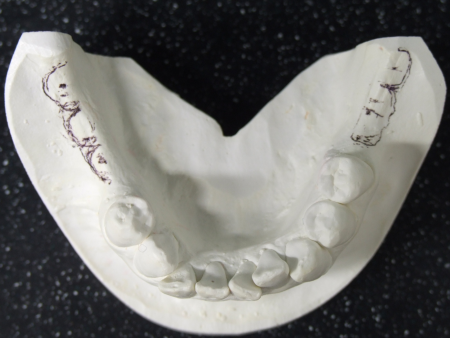

したがって右下前歯を動かさない計画のもと右下前歯の位置を基準としてそれ以外の歯を並べ直して理想的な歯並び、噛み合わせを再現した「セットアップ模型」を製作しました。

セットアップ模型:患者様の歯型をもとに作製した模型の歯の部分を切りだしてバラバラにしてから理想的な位置に並べ直して、咬合治療のゴールをシミュレーションし、確認するために用います。

このセットアップ模型を計測することでインプラントを埋入しなければならない正しい位置を知ることができます。

☆今回は右下前歯の位置を動かさない計画でしたので、治療前の右下前歯の位置を基準にインプラント埋入位置を決定しました。もし下顎の前歯を後方に移動したり、正中を変更したりする計画の場合にはこの移動量を加味してインプラント埋入位置を算定する必要があります。

PA分析では、挺出した左上第1大臼歯によって左右の上顎第一大臼を歯結んだ咬合平面に極端な右上がりの傾斜(キャント)が発生しています。咬合治療の進め方としてはまず左上ブリッジの支台歯(犬歯、第2小臼歯)をTEKに変更(一般歯科担当医)とインプラント4本それぞれにTEKの装着(インプラント専門医)を行いました。上下に矯正装置を装着するタイミングでオーバーレイテクニックを行い、下顎骨のスイングバック量を評価しながら咬合治療のゴール設定である咬合平面、咬合高径を決定します。この咬合平面を基準に左上第1大臼歯の圧下を行っています。